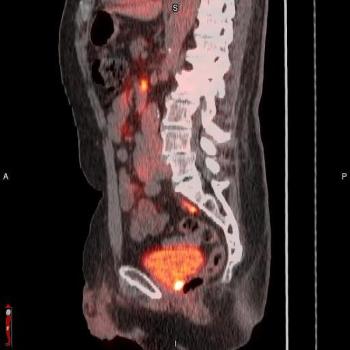

For patients 80 years of age or older that have a PSA level at 20 ng/mL or higher, PSMA PET/CT has a high likelihood of success in diagnosing and staging prostate cancer regardless of pre-imaging biopsy use, according to newly published research.